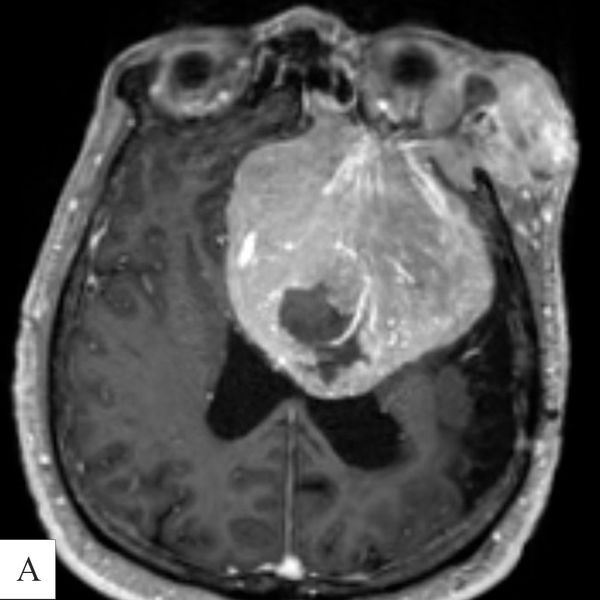

- Контрольной МРТ головного мозга с контрастированием (в апреле 2024 года): объёмное образование размером 80 × 79 × 90 мм в области латеральных отделов большого крыла клиновидной кости.

- МРТ головного мозга с контрастным усилением: менингиома, которая широким основанием прилегает ко дну передней черепной ямки слева и распространяется в левую среднюю черепную ямку. Опухоль прорастает в лобную кость и выходит из черепа в мягкие ткани головы, в латеральные отделы левой орбиты (глазницы) и левую лобную пазуху. Размеры опухоли — 85 х 75 х 79 мм (объём — около 250 см3).